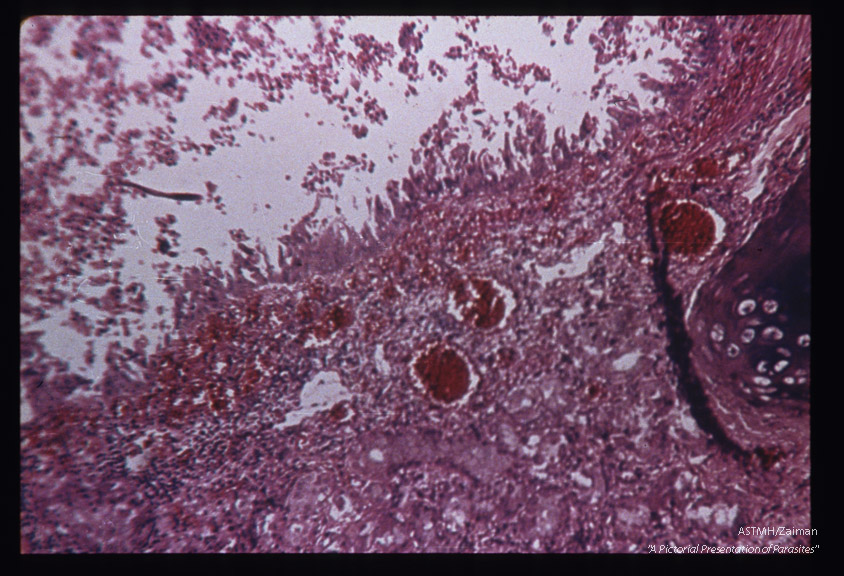

Hematoxylin-eosin stained section of human lung showing larva in alveolus.

Strongyloides stercoralis

Description: Hematoxylin-eosin stained section of human lung showing larva in alveolus.